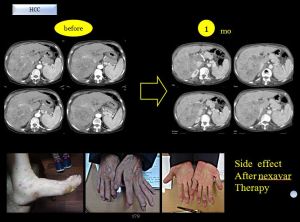

%eb%84%a5%ec%82%ac%eb%b0%94